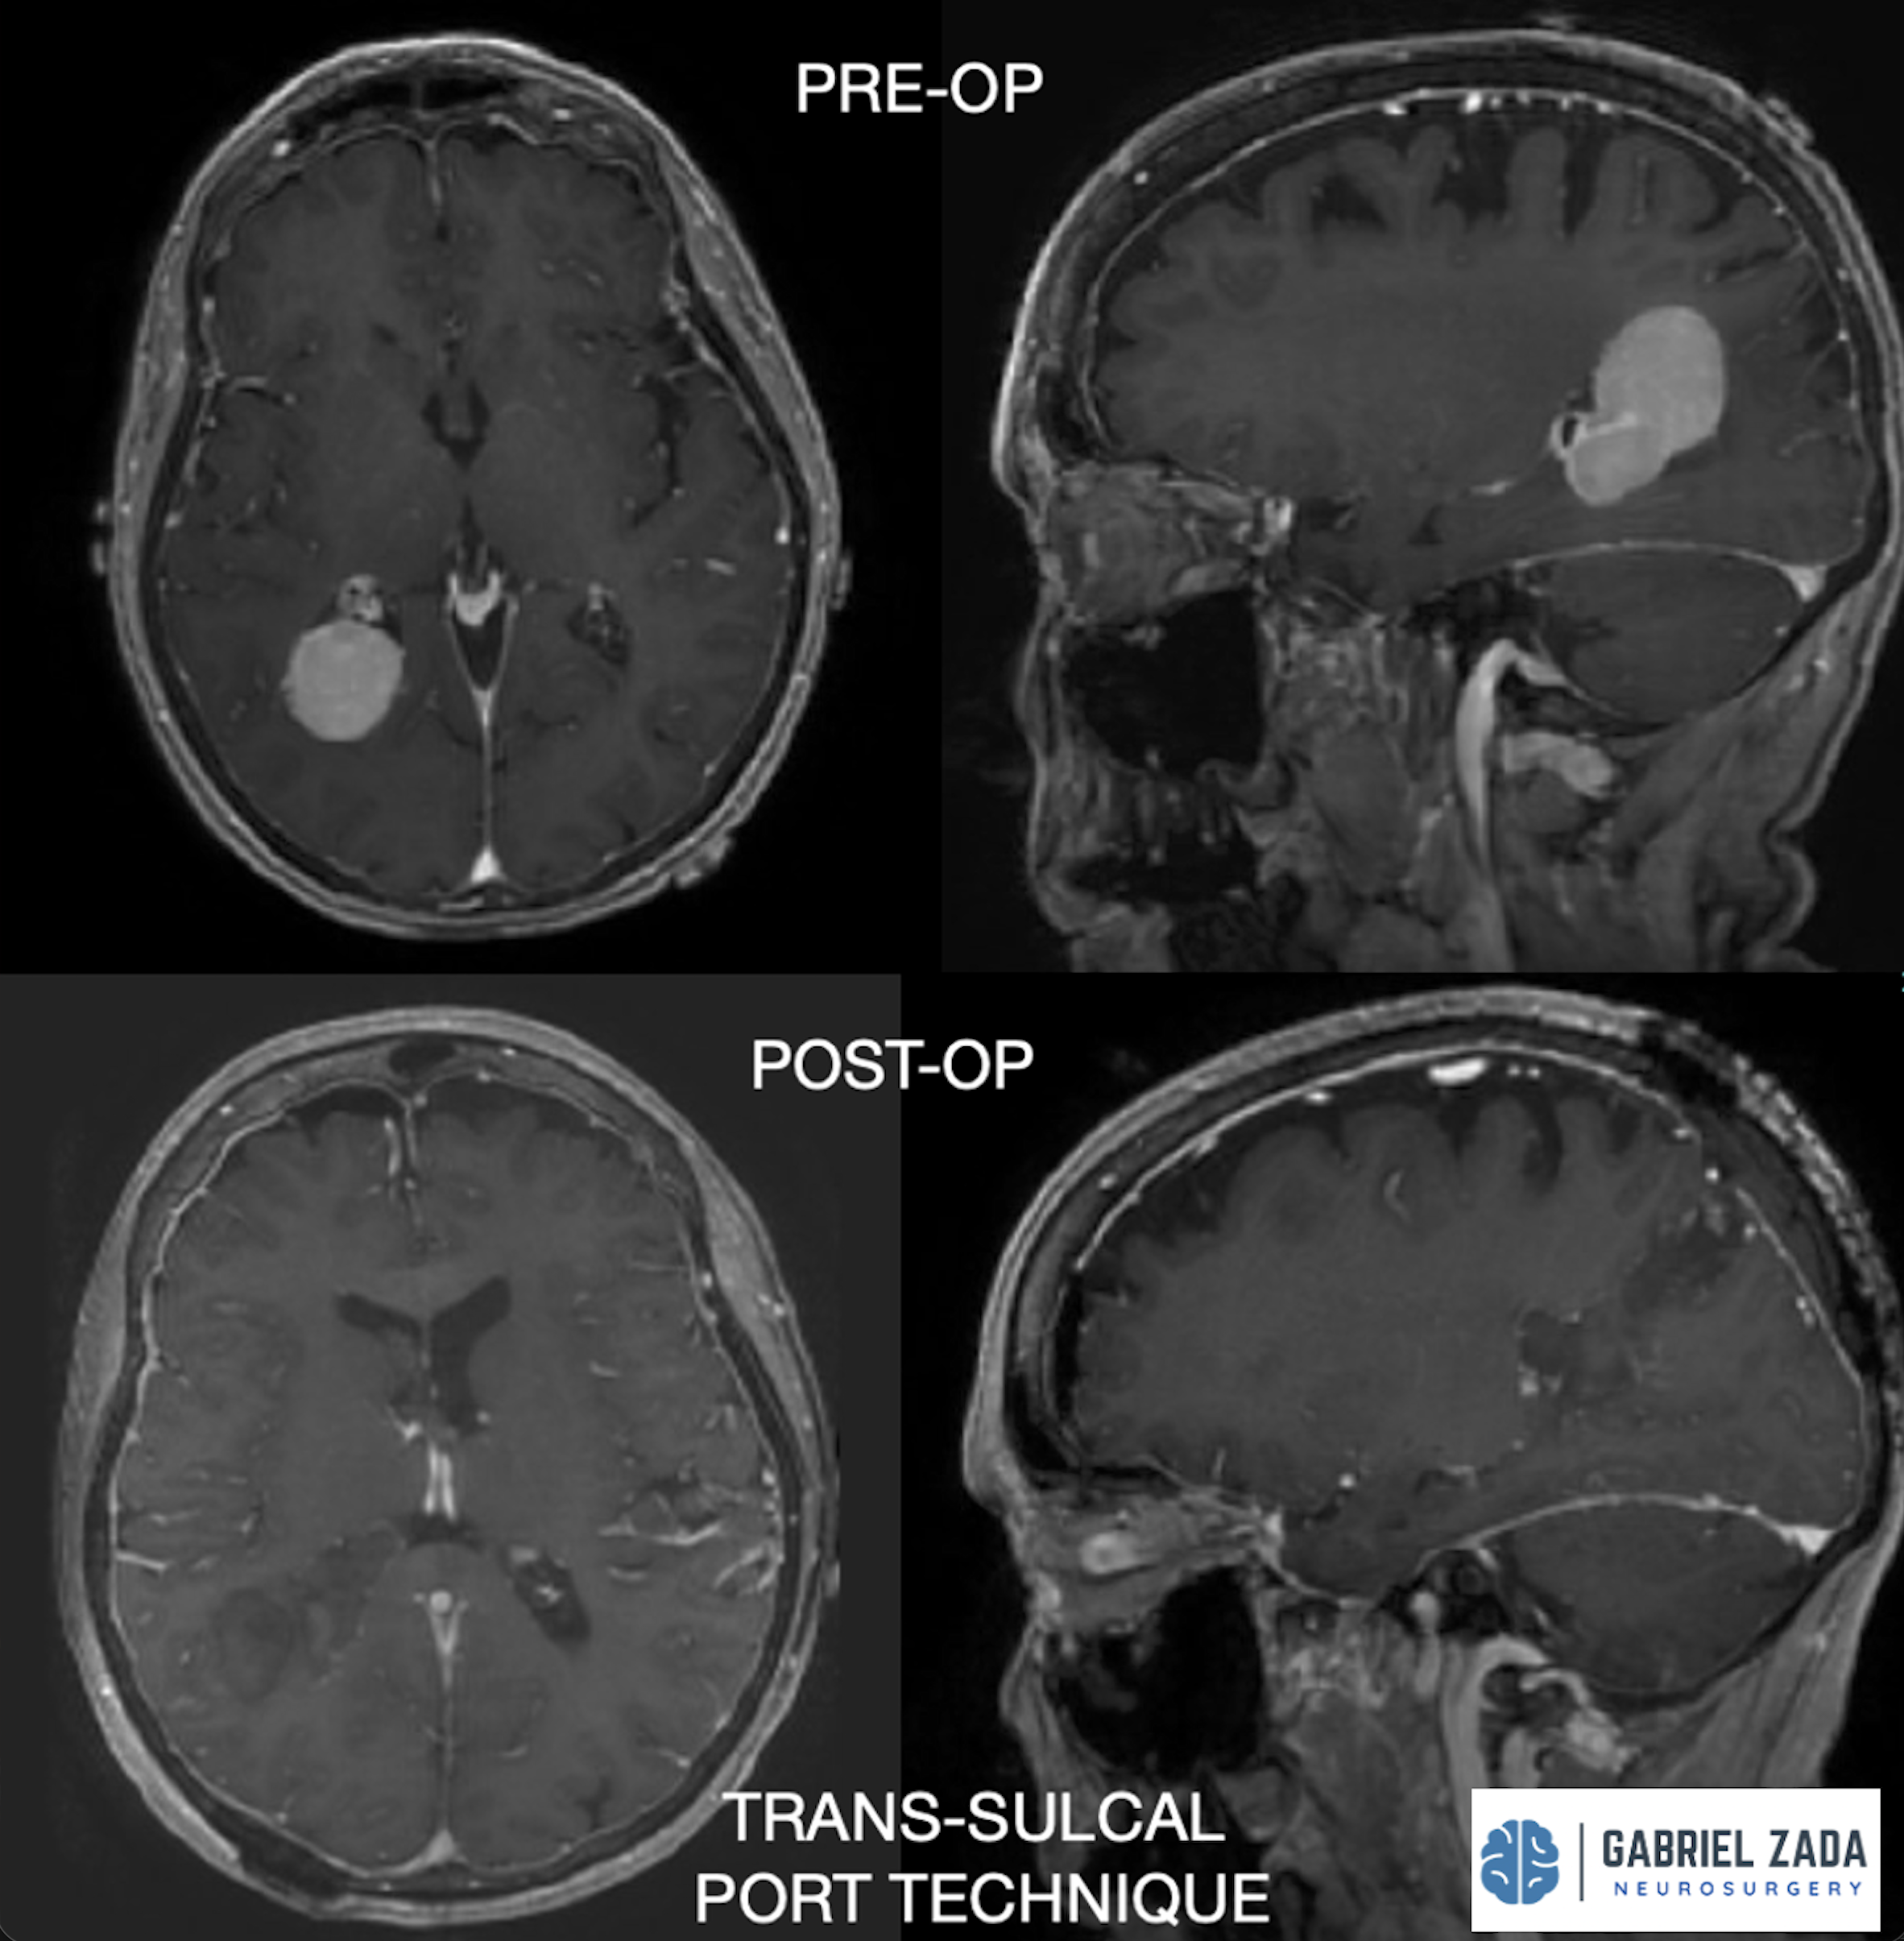

Explore this comprehensive gallery featuring pre‑ and post‑operative imaging of patients with skull‑base tumors treated by Gabriel Zada, MD, MS, FAANS, FACS. These cases highlight Dr. Zada’s expertise in advanced neurosurgical techniques and outcomes.

*Representative cases shown for educational purposes. All images de-identified. Individual results vary.